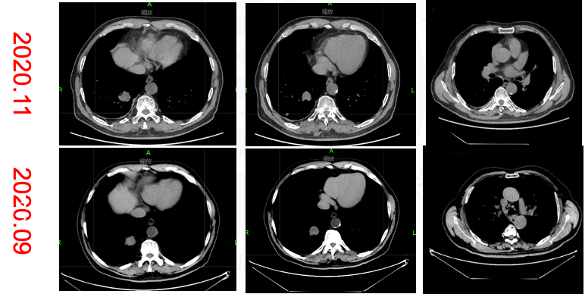

√ 2021.06.28胸部CT:右肺下叶后基底段肿块约21×23×21mm大小,右肺下叶后基底段(Img230)见结节影,大小为7×7mm,较前缩小。疗效评价PR。

2022.05.06 胸部CT:右肺下叶后基底段肿块约13×17×18mm大小,较前(22.02)明显缩小,疗效评价PR,未再发生间质性肺炎。